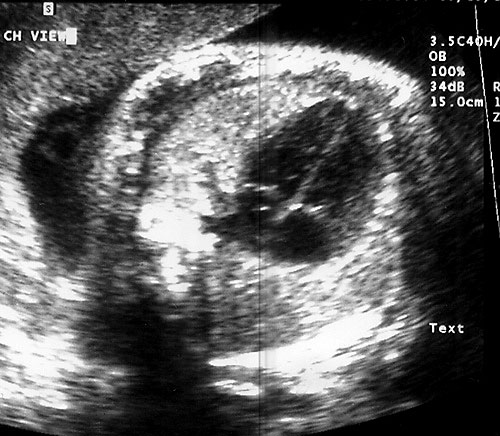

- Biparietal Diameter (BPD)/Head Circumference (HC)/Intracranial Anatomy — Ventricles/Atria/Posterior Fossa

- Measuring BPD/HC

- Axial plane at level of septum cavum pellucidum and thalamic nuclei. (Shepard M, Filly RA. A standardized plane for bieparietal diameter measurement. J Ultrasound Med 1982;1(4):145-50.)

Normal BPD at level of thalami with cavum seen. - Falx: midline and perpendicular to angle of insonation. (Simpson GF, Filly RA. Comparison of fetal head circumference measurements using standard and long linear array transducers. J Diagn Med Sonogr 1988;4:2)